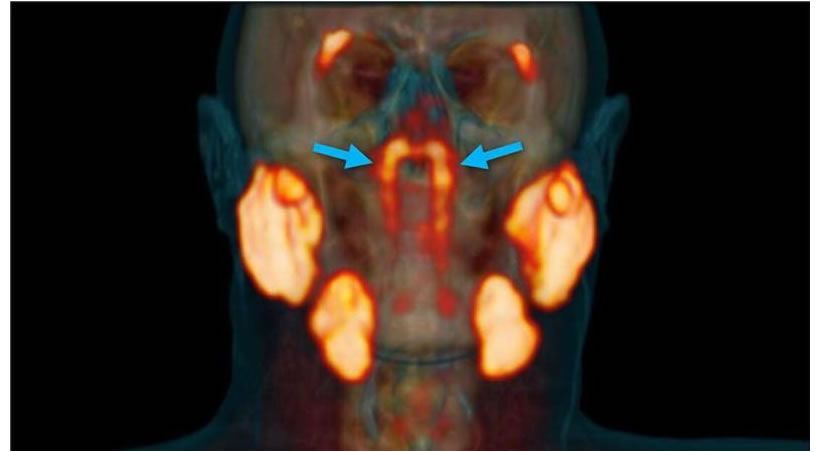

Infección odontológica y morbimortalidad en cirugía cardíaca valvular

Se recomienda el screening dental preoperatorio